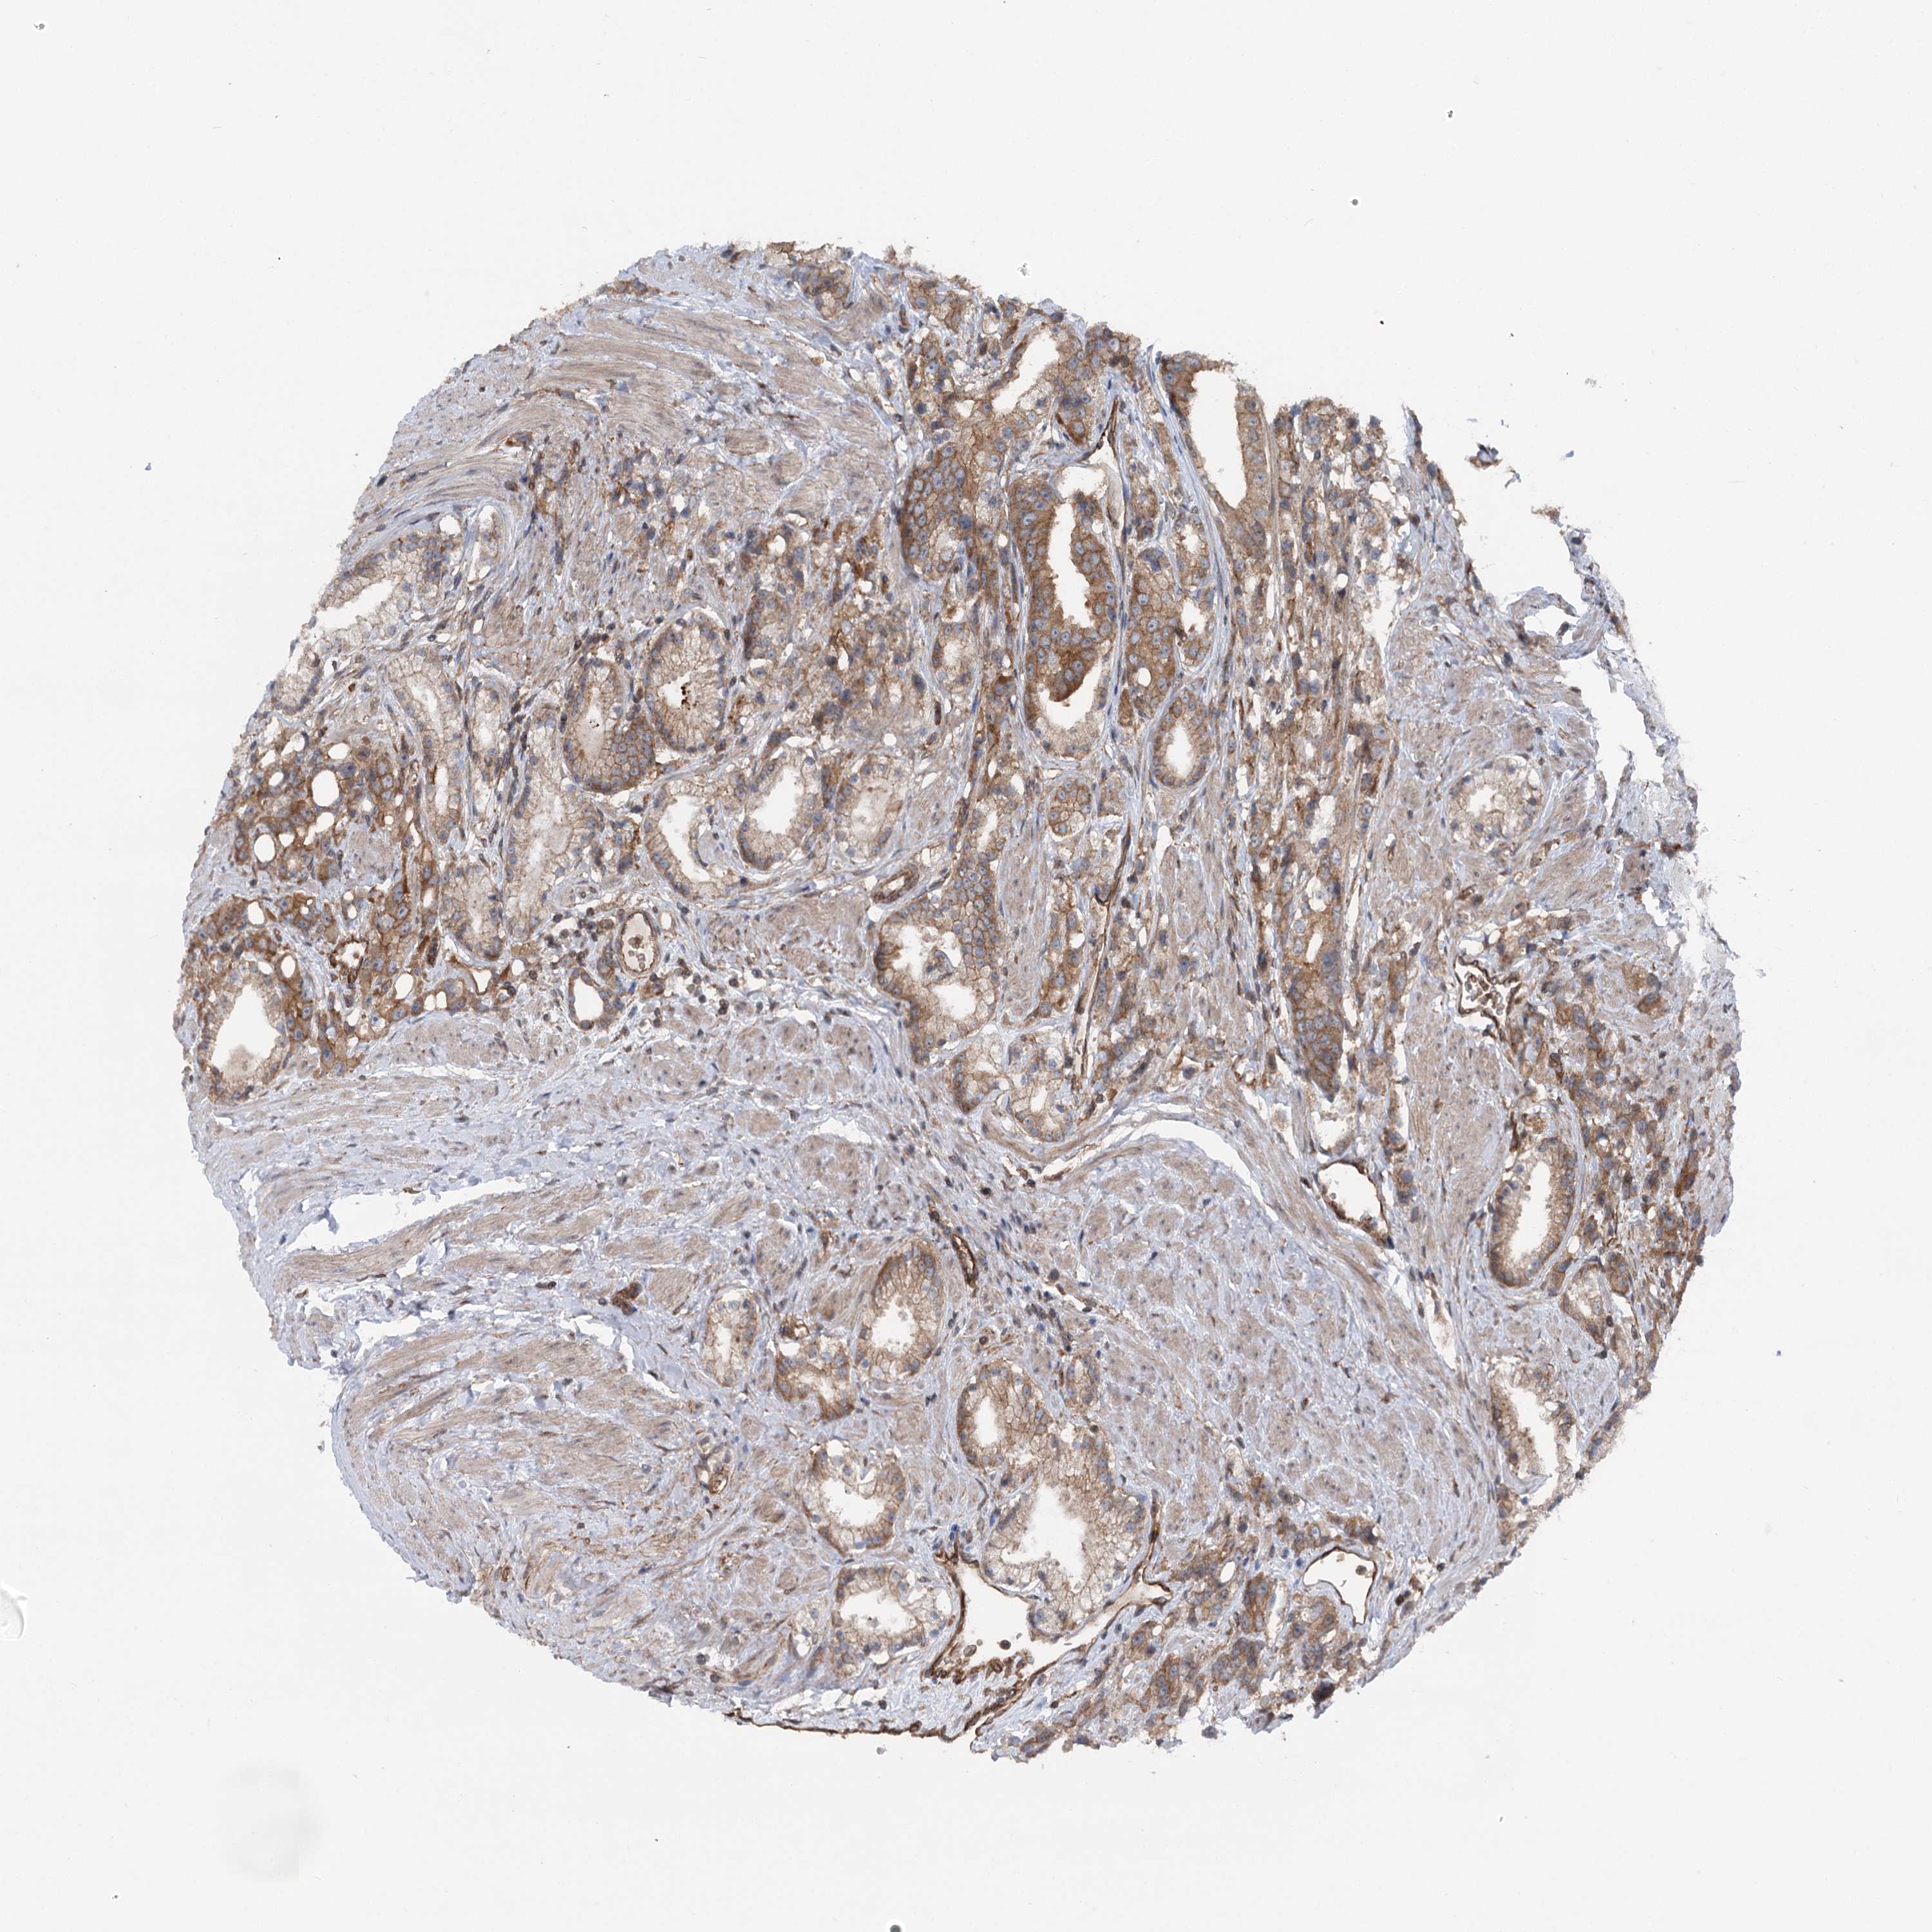

PROSTATE CANCER - Protein expressioni

A mouse-over function shows sample information and annotation data. Click on an image to view it in a full screen mode. Samples can be filtered based on level of antibody staining by selecting one or several of the following categories: high, medium, low and not detected. The assay and annotation is described here.

Antibody stainingi

Antibody staining in the annotated cell types in the current human tissue is reported as not detected, low, medium, or high, based on conventional immunohistochemistry profiling in selected tissues. This score is based on the combination of the staining intensity and fraction of stained cells.

Each image is clickable and will lead to virtual microscopy that enables deeper exploration of all samples and also displays staining intensity scores, fraction scores and subcellular localization as well as patient and tissue information for each sample.

Antibody HPA038143

Antibody HPA038144

Staining

High

Medium

Low

Not detected

Intensity

Strong

Moderate

Weak

Negative

Quantity

>75%

75%-25%

<25%

None

Location

Nuclear

Cytoplasmic/membranous

Cytoplasmic/membranous,nuclear

Adenocarcinoma, NOS

Adenocarcinoma, High grade

Adenocarcinoma, Low grade